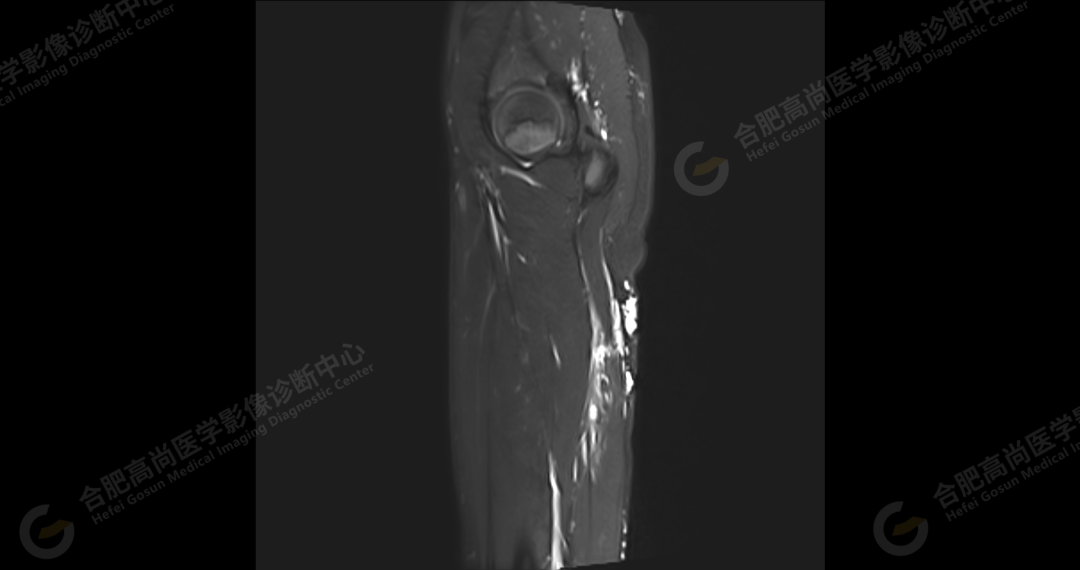

左侧髂骨内侧及闭孔内肌前方可见网格状异常信号影,边界欠清,T1WI 呈低信号,T2 压脂呈高信号,病变连续,延伸至臀肌内;左侧臀肌间隙及皮下、左大腿后部肌肉群及皮下、左膝前外侧及腘窝皮下、左小腿后侧皮下累及比目鱼肌及内外侧腓肠肌、左内外踝皮下、左足背足底及左足肌间隙内可见大片状、结节状弥漫性异常信号影,形态不规则,分布不均匀,边界不清,T1WI 呈低信号,T2WI 压脂后病灶呈高信号,部分病灶内可见网格状低信号,左足部肌间隙增宽,第 2-4 跖骨稍受压,骨质结构完整。左髋关节、膝、左踝关节间隙正常,无明显狭窄及增宽,关节面光滑,关节腔内无积液,左股骨、胫腓骨及踝部各组成骨骨质结构完整,未见明显异常改变。

左侧盆腔及下肢皮下及部分肌间隙内漫状血管瘤,请结合临床。